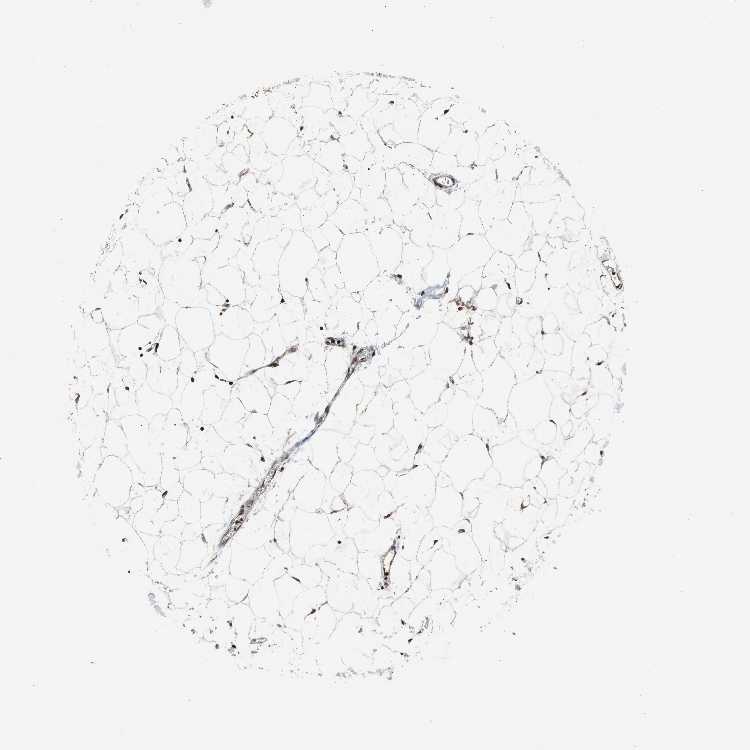

SOFT TISSUE 2 - Antibody stainingi

Antibody staining in the annotated cell types in the current human tissue is reported as not detected, low, medium, or high, based on conventional immunohistochemistry profiling in selected tissues. This score is based on the combination of the staining intensity and fraction of stained cells.

Each image is clickable and will lead to virtual microscopy that enables deeper exploration of all samples and also displays staining intensity scores, fraction scores and subcellular localization as well as patient and tissue information for each sample.

Antibody HPA000898Antibody CAB005219

Fibroblasts MediumMedium

Peripheral nerve High-